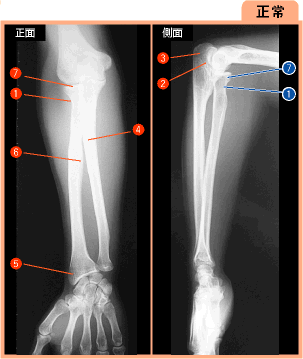

▲260ページ 正常画像 側面 内(2007/2/5)

※1の引き出し線を修正,7の引き出し線を追加(下は修正済みの画像です.青い線で示しています)

| ● |

|